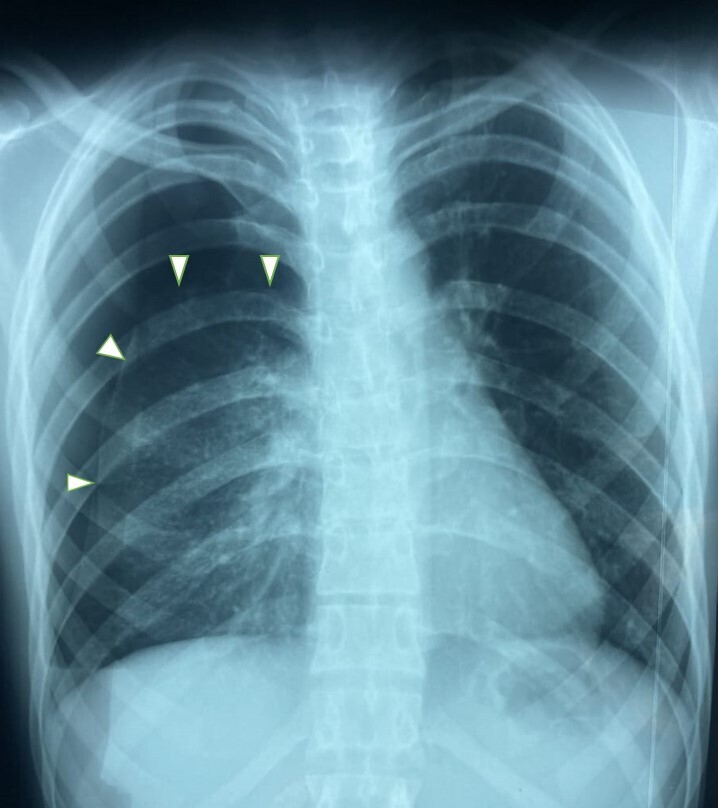

Une femme de 38 ans, sans antécédents particuliers, consulte pour des douleurs thoraciques récurrentes du côté droit, survenant de manière synchrone avec ses menstruations.

Quel est votre diagnostic ?

Il s’agit d’un pneumothorax cataménial : c’est une condition peu fréquente et méconnue, caractérisée par la survenue récurrente de pneumothorax généralement entre la veille et les 72 h suivant le début des menstruations. Dans la majorité des cas, il affecte le côté droit, mais des cas du côté gauche voire bilatéraux ont également été signalés.

En pratique, la combinaison typique de douleurs thoraciques, de dyspnée et d’hémoptysie survenant dans les 72 heures avant ou après les menstruations chez les jeunes femmes devrait inciter les praticiens à évoquer un pneumothorax cataménial.